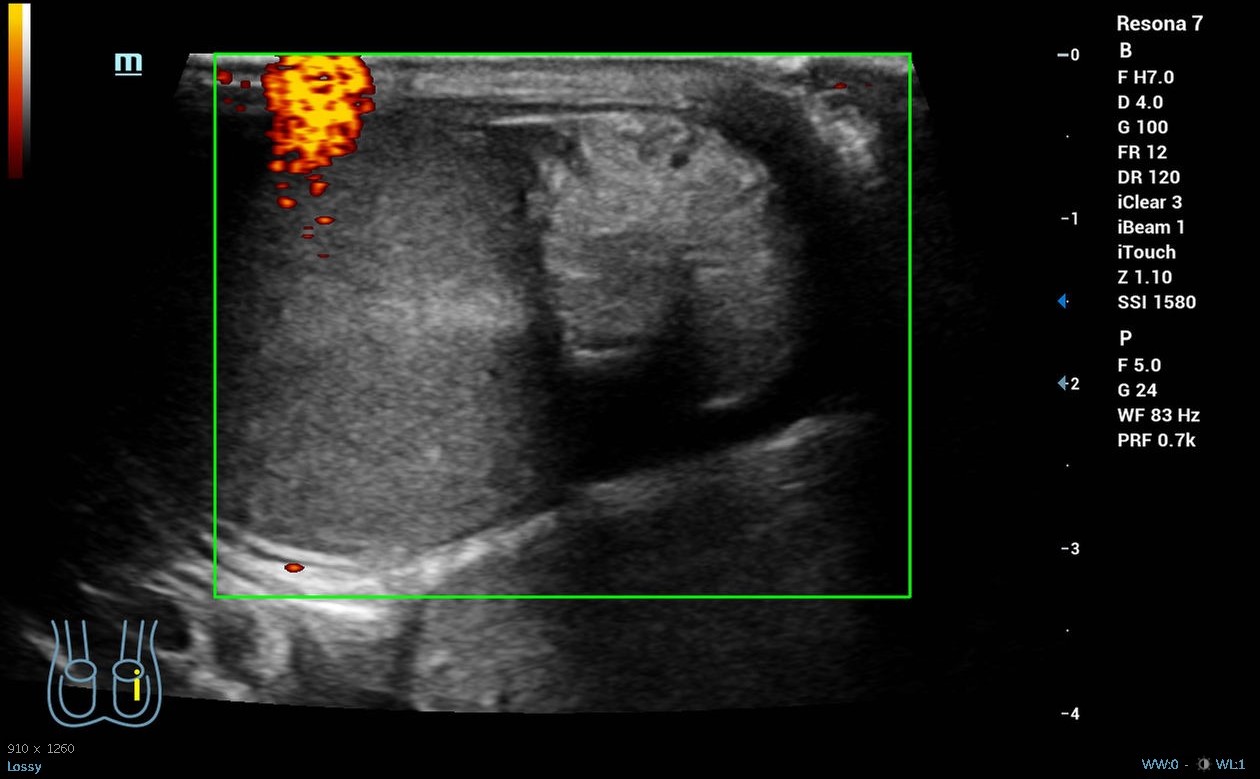

Hombre de 19 años sin antecedentes de interés que acude a la guardia del centro de salud por dolor súbito en el testículo derecho desde las 04.00 h que le ha despertado, asociado a náuseas y vómitos, sin otra clínica infecciosa o traumática acompañante. A la exploración física presenta abdomen normal, pero teste izquierdo ascendido y horizontalizado, doloroso a la palpación, con discreto aumento de tamaño o cambios en temperatura, con signo de Prehn negativo y reflejo cremastérico ausente en lado izquierdo. Se realiza ecografía clínica, donde se objetiva testículo izquierdo aumentado de tamaño con morfología y ecoestructura normal, pero con ausencia de flujo power-Doppler en su interior, ligero hidrocele y aparente giro del cordón espermático en su porción distal.

Derivación hospitalaria urgente, donde se corroboran los hallazgos de la ecografía clínica y se realiza detorsión quirúrgica.